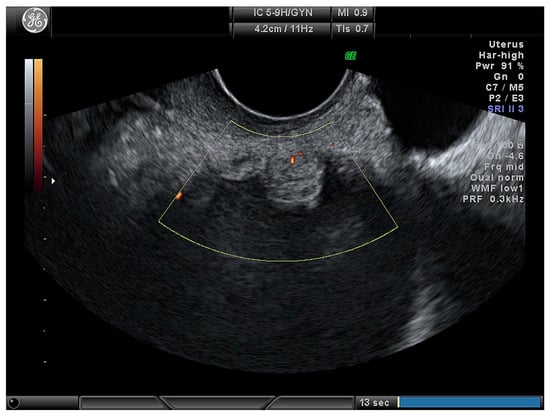

| Cystic–solid (Figure 4) | 61 (71.8) |